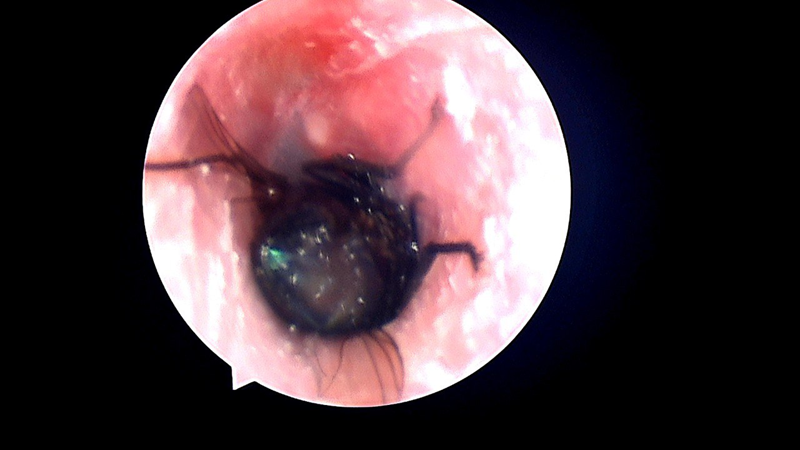

Nội soi tai mũi họng: quan sát được cấu trúc amidan cũng như hệ thống tai mũi họng.